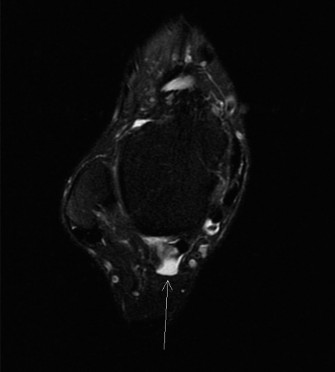

A 31-year-old female presents to your office with increasing pain over the posterior medial ankle and stiffne…